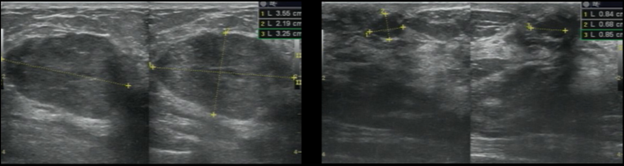

Bệnh nhân: 56 tuổi.

Tình trạng: Khối giảm âm, giới hạn rõ.

Kết quả:

- HHUS: Chỉ ghi nhận một khối giảm âm - BI-RADS 3.

Hình 8. Khối giảm âm, giới hạn rõ trên HHUS

- ABUS: Ngoài khối u trên còn phát hiện thêm một khối giảm âm không đều, có gai nằm ngay phía sau - BI-RADS 4

Hình 9. Khối giảm âm, bờ rõ quan sát thấy trên ABUS (mũi tên vàng) và khối giảm âm, bờ không đều và có tua gai nằm ngay phía sau (mũi tên cam) – BI-RADS 4

Kết quả mô bệnh học: Sẹo hình tia (Radial scar)

Ý nghĩa lâm sàng: Với lát cắt và mặt phẳng quan sát đặc trưng (ví dụ coronal view) dày 2mm, ABUS cung cấp “bản đồ” cấu trúc mô vú rõ ràng hơn, giúp nhận diện các biến đổi kiến trúc mà siêu âm 2D đôi khi khó thể hiện trọn vẹn.